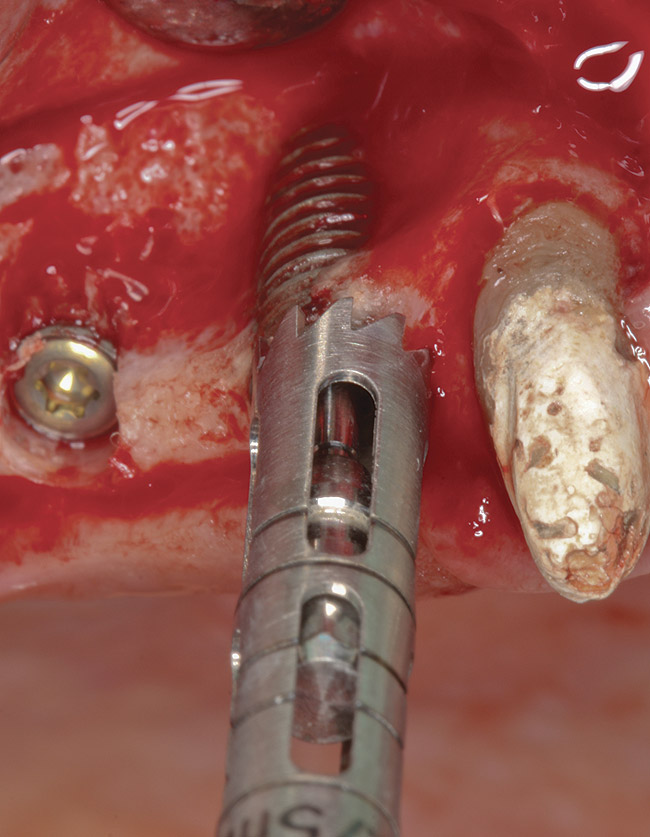

Figure 3  The implant was explanted by using a counter-torque ratchet.

Figure 3